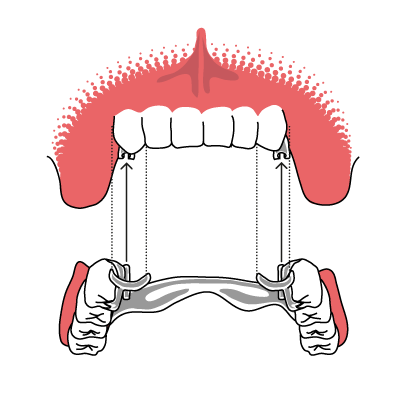

Teleskopprothese auf Kronen